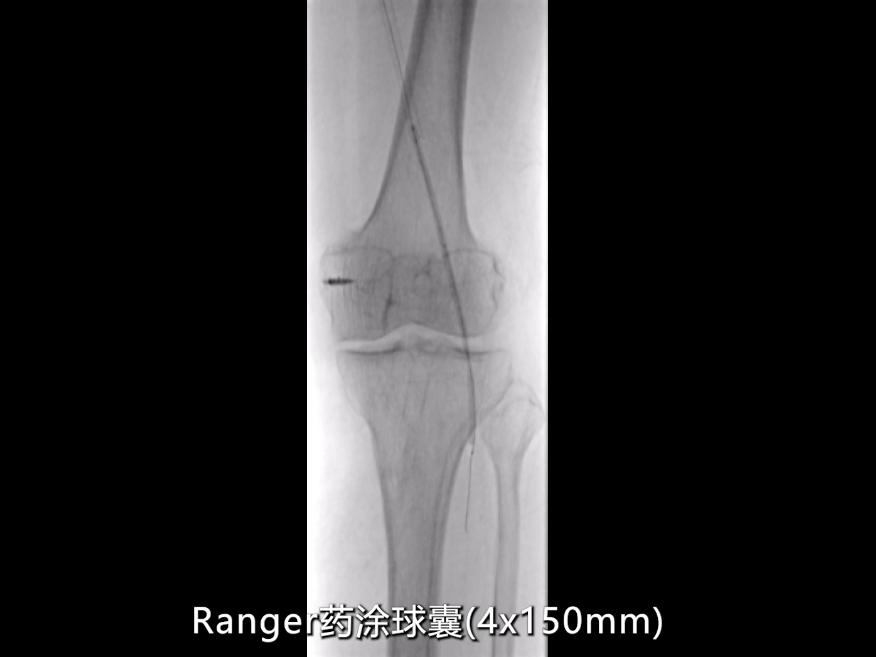

药物涂层球囊强化:

针对CT测量提示的股动脉远端及腘动脉段(直径约5mm),使用4×150mmRanger药物涂层球囊扩张;